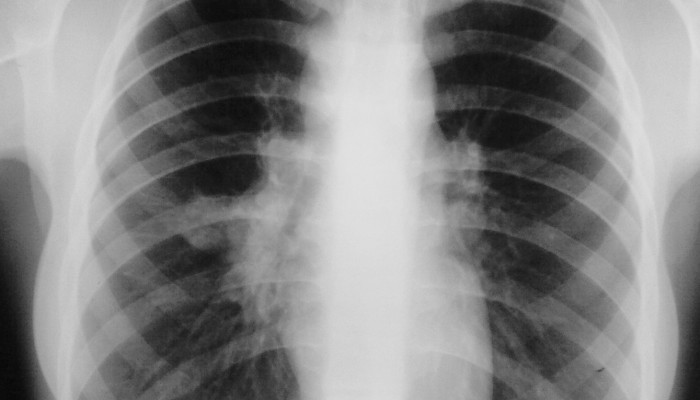

Чаще всего в практике встречается рентгенография грудной клетки, вариант которой (флюорографию) взрослый человек должен проходить раз в год. На получаемых снимках, вопреки заблуждениям, изучается не только состояние лёгких. Рентгенологи описывают как внешние костные структуры, так и содержимое грудной клетки. Поэтому одним снимком можно не только исключить одно заболевание, но и выявить совершенно другое.

Что показывает рентген грудной клетки? При первом же взгляде внимание сразу задерживается на очертаниях скелета, которые выделяются на фоне тёмной лёгочной ткани. Кости хорошо задерживают излучение, поэтому на снимке они видны в форме ровных и светлых полос. Их состояние оценивается в следующем порядке:

- Начинается диагностика с оценки состояния лёгочной ткани – она производится поочерёдно в каждом промежутке между рёбрами с правой и левой стороны. В норме этот орган практически не виден на рентгенограмме, что объясняется большим содержанием в нём воздуха. Поэтому излучение быстро проходит его, практически не оставляя следов на плёнке.

При осмотре симметричных лёгочных полей в первую очередь учитывается их однородность. Если всё же подозревается какое-либо отклонение, то его сравнивают только с аналогичным участком другого лёгкого. Чаще всего при патологии встречаются следующие изменения:

Большинство рентгенологических симптомов описано именно относительно заболеваний лёгких, что ставит этот метод исследования на первое место в диагностике патологии органов дыхания.